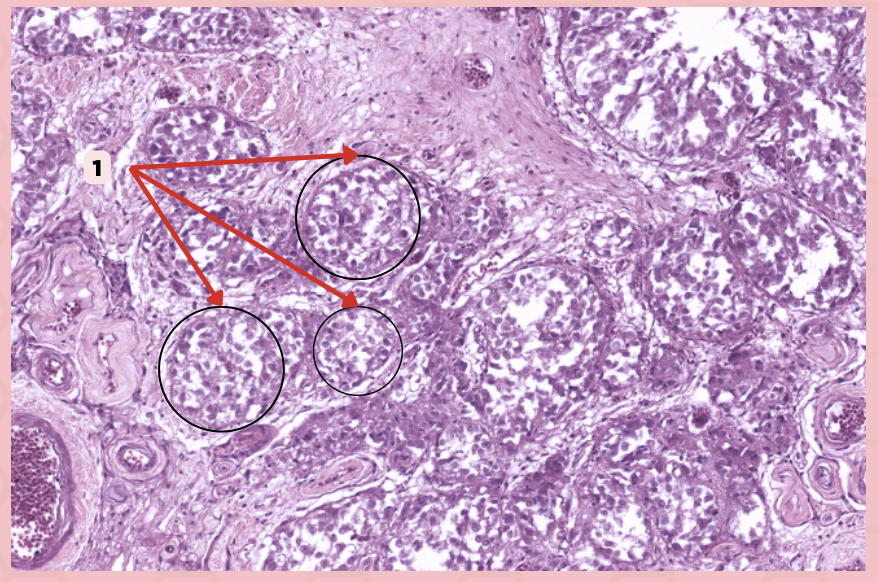

Identify the specimen.

Lobule

Identify the structure labeled as 1.

#5 Pinealocytes (Chief Cells)

Which among these structures are modified neurons that are responsible for synthesizing melatonin?

#1 Interstitial Cells

Which among these are supporting cells that are morphologically similar to astrocytes?

Interstitial Cells

Identify the structure labeled as 1.

Clusters (Cords) of Cells

Identify the structure labeled as 2.

Capillaries

Identify the structure labeled as 3.

Lobule

Identify the structure labeled as 4.

Pinealocyte

Identify the structure labeled as 5.